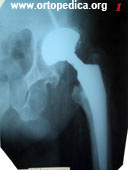

1,2. Перелом бедренной кости ниже уровня эндопротеза